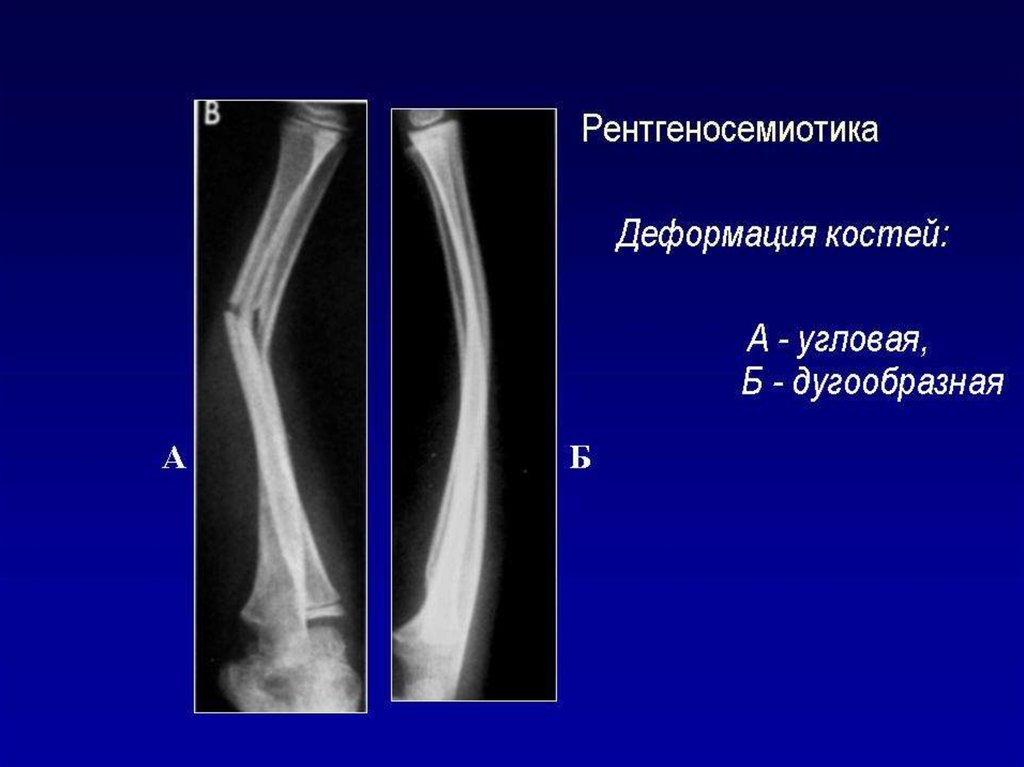

Лучевое исследование костно-суставной системы. Методы исследования. Семиотика